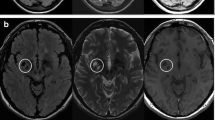

Machine specifications

The study was conducted at three different centers in upper Egypt, all of which were equipped with a Philips Achieva 1.5 T MRI machine. MRI acquisition was done with the same methodology. A T1-weighted spin-echo axial picture (TR/TE = 600/15 ms, flip angle = 90°, FOV (frequency/phase) = 220/75, acquisition matrix size = 256 256, voxel size = 1 1 3 mm) and a T2-weighted FLAIR (fluid-attenuated inversion recovery) image (TR/TE = 9000/110 ms, inversion time = 2500 ms, flip angle = 130◦, FOV (frequency/ phase) = 220/75, acquisition matrix size = 320 × 168, voxel size = 1 × 1 × 3 mm) were collected, and they covered the whole brain so that we could calculate the volumes of the brain and any lesions present.

The volumetric data was obtained through the acquisition of magnetic resonance imaging (MRI) data, including T1 and FLAIR sequences. These sequences were converted from Digital Imaging and Communications in Medicine (DICOM) files to two compressed, anonymized Neuroimaging Informatics Technology Initiative (NIfTI) files—one for T1 and the other for FLAIR—which were used for subsequent analyses.

Brain volume and lesion load assessment

LesionBrain 1.0 is an accessible web-based application that has been designed specifically for the segmentation of white matter lesions45. This software has been successfully integrated into the volBrain platform (https://volbrain.upv.es/)46, providing a comprehensive tool for the accurate and efficient detection of lesions. The processing pipeline is comprised of several crucial steps, including image normalization and registration, structure segmentation to identify the intracranial cavity, brainstem, cerebellum, and lateral ventricles, and candidate mapping to identify areas that may potentially contain lesions. The lesions are then segmented using a voxel-wise method, which employs a three-step approach comprising patch-based multimodal segmentation, patch-based regularization of the generated lesion probability map, and an ensemble of shallow neural networks to rectify any erroneous patches, thereby minimizing false positives. Importantly, this pipeline has been rigorously evaluated using the MSSEG MICCAI Challenge 2016 dataset and has demonstrated good performance, with a mean Dice coefficient of 0.6647. The whole brain volume, total numbers of lesions, the absolute volume of all lesions either total or regional (in cubic centimeters) were all measured.